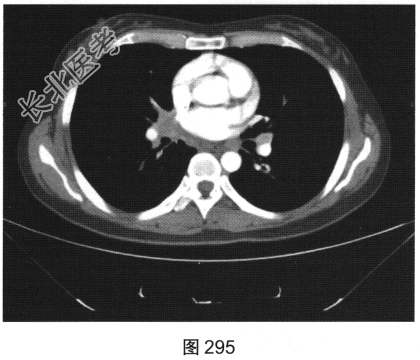

- [材料题] 患者女性,43岁,因“确诊肺低分化腺癌1周”就诊。患者于2014年11月无明显诱因出现咳嗽、咳痰,无胸闷胸痛,无咯血,无发热、乏力、体重减轻等。自服中药治疗,止咳效果尚可。2015年4月22日在山海关人民医院行胸部CT:显示①慢性支气管炎继发感染,建议结合临床及病史考虑;②右侧中间段支气管及中叶支气管壁增厚、管腔狭窄伴右肺中叶阻塞性肺不张,右侧肺门及纵隔多发淋巴结增大,建议增强扫描。后补做增强CT:右肺中叶支气管增厚,管腔狭窄伴阻塞性肺不张,考虑右侧中心型肺癌伴纵隔多发淋巴结增大,建议行支气管镜检查。支气管镜取活检病理:示低分化腺(右肺中叶)癌,建议做免疫组织化学检测,以进一步明确诊断。于北京肿瘤医院行PET/CT检查:①右肺中叶支气管起始部位高代谢结节,符合中心型肺癌表现;右肺中叶部位阻塞性不张,不张肺内高代谢结节,倾向肺内转移;双肺多发转移结节;双锁骨上区、左胸肌间、纵隔及双肺门多发淋巴结转移。②脑部未见明显高代谢征象,建议行增强MRI检查。③双叶甲状腺炎性或非特异性摄取,建议行B超及甲状腺功能检查。患者精神状态良好,体力、食欲、睡眠均正常,体重无明显变化,大便、排尿正常,为进一步检查及治疗,门诊以“肺癌”收入院。2015年5月5日在我院行CT检查,如图288~图295所示。